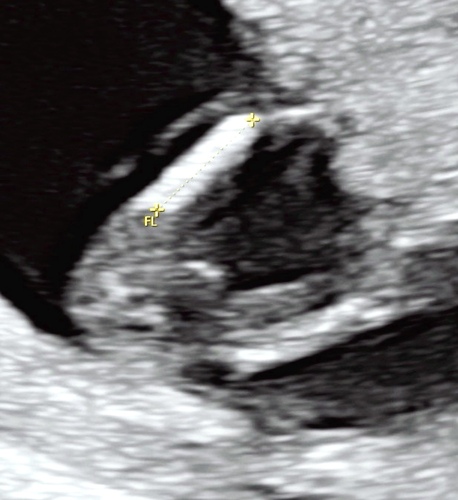

Wat denken jullie? 😁

Ik denk ook een meisje, bij een jongen zou je in die positie denk ik echt al een pipi zien!